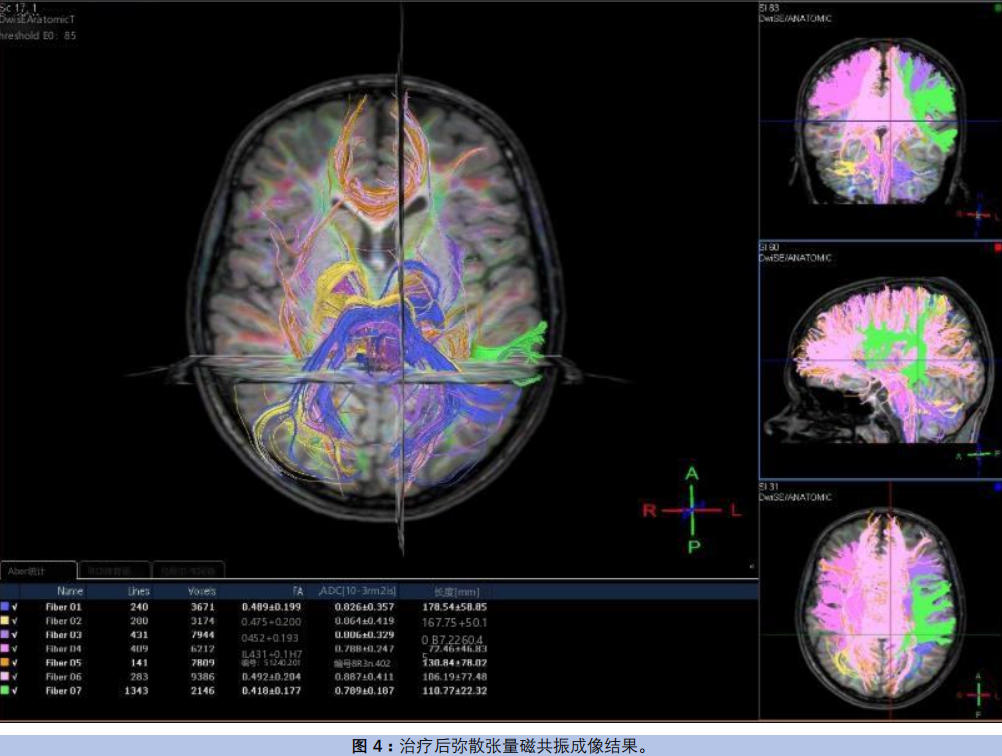

弥散张量磁共振成像变化(图4):胼胝体联络纤维FA值升至0.492±0.204,弓状束FA值升至0.418±0.177,皮质脊髓束FA值同步提升。脑白质微结构改善与语言、社交功能好转呈显著相关,证实神经连接得到有效修复。